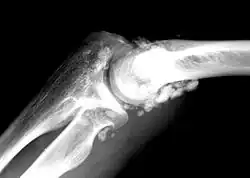

X-ray of an elbow affected by synovial chondromatosis

Synovial chondromatosis is a locally aggressive bone tumor of the cartilaginous type.[1] It consists of several hyaline cartilaginous nodules and has the potential of becoming cancerous.[1]

Rare and little known, with currently no known cure, the disease gradually forms blisters in the thin flexible membrane of the synovium, which calcify and enlarge. These nodules eventually break free and float around the joint space becoming larger – these add to the discomfort and stiffness of the joint. The affected tissue will show up as a semi-solid mass in an MRI scan, final diagnosis is usually confirmed by taking a biopsy. The disease generally affects only one of the larger weight bearing joints (hip, ankle, knee) – although the elbow, and wrist can also be affected. It rarely involves the temporomandibular joint (TMJ) and most publications are case reports.[3]